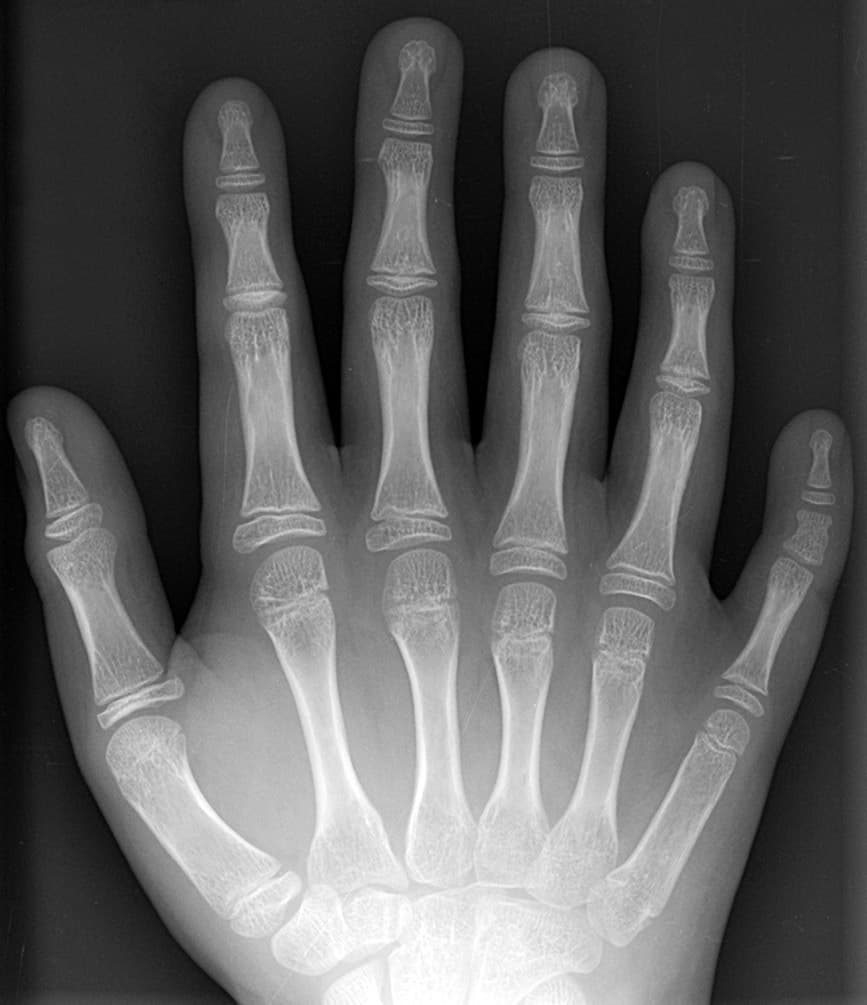

Para confirmarlo, en ocasiones se realizan análisis de laboratorio de diversos tipos, entre ellos pruebas enzimáticas, estudios metabólicos, cromosómicos y radiografías.